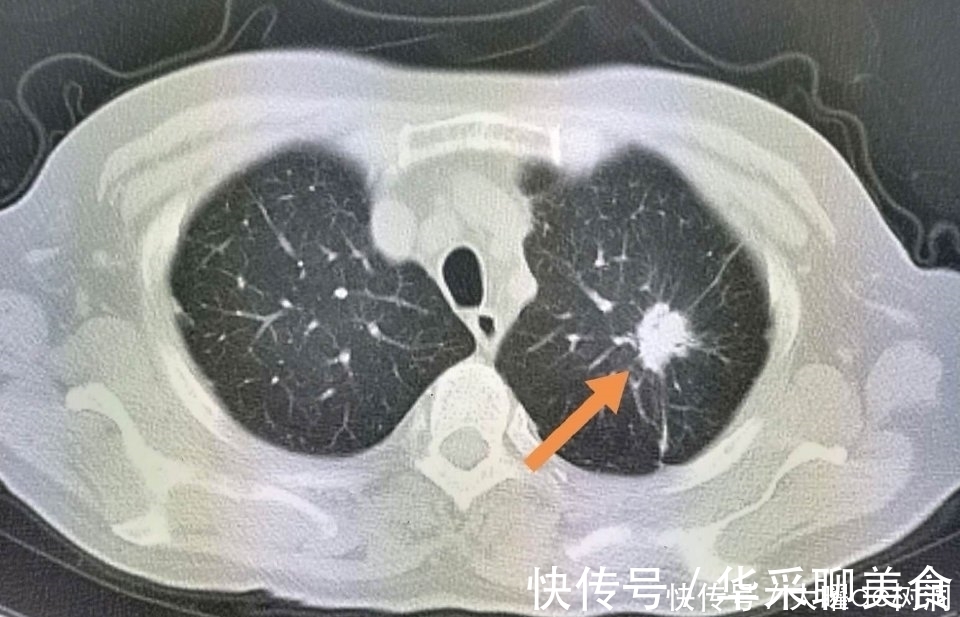

再看一个比较遗憾的病人:

文章插图

这位66岁的女士,钡餐体检时意外发现左肺尖高密度影。

这里的病灶常见于肺结核、尘肺等,但必须进一步CT检查除外肺癌。

遗憾的是老太太没有进一步检查,自述年轻的时候曾经经常咳嗽,也许是得过肺结核,自愈了?

结果一年以后,病灶长大了:

并且发生了淋巴结转移,不能手术了。